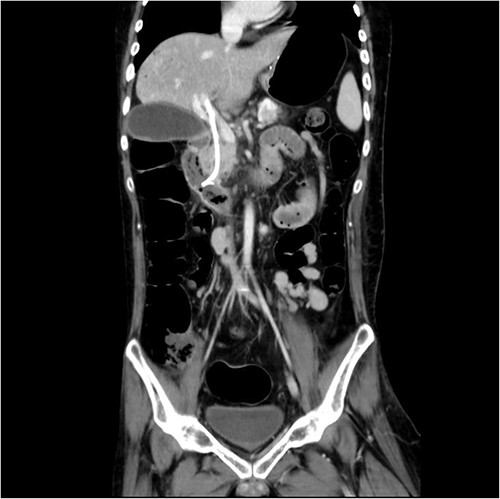

Initial laboratory findings revealed significant hyperbilirubinemia, liver enzyme elevation and mild PT prolongation. Abdominal computed tomography showed a CBD stone caused obstruction, resulting in upstream biliary dilatation and acute cholecystitis (Fig. 1). Besides, small caliber of inferior vena cava, splenic vein, and right iliac veins with thrombosis and prominent collaterals formation was also shown on the image.

Abdominal CT revealed CBD stone resulting in upstream biliary dilatation and acute cholecystitis.